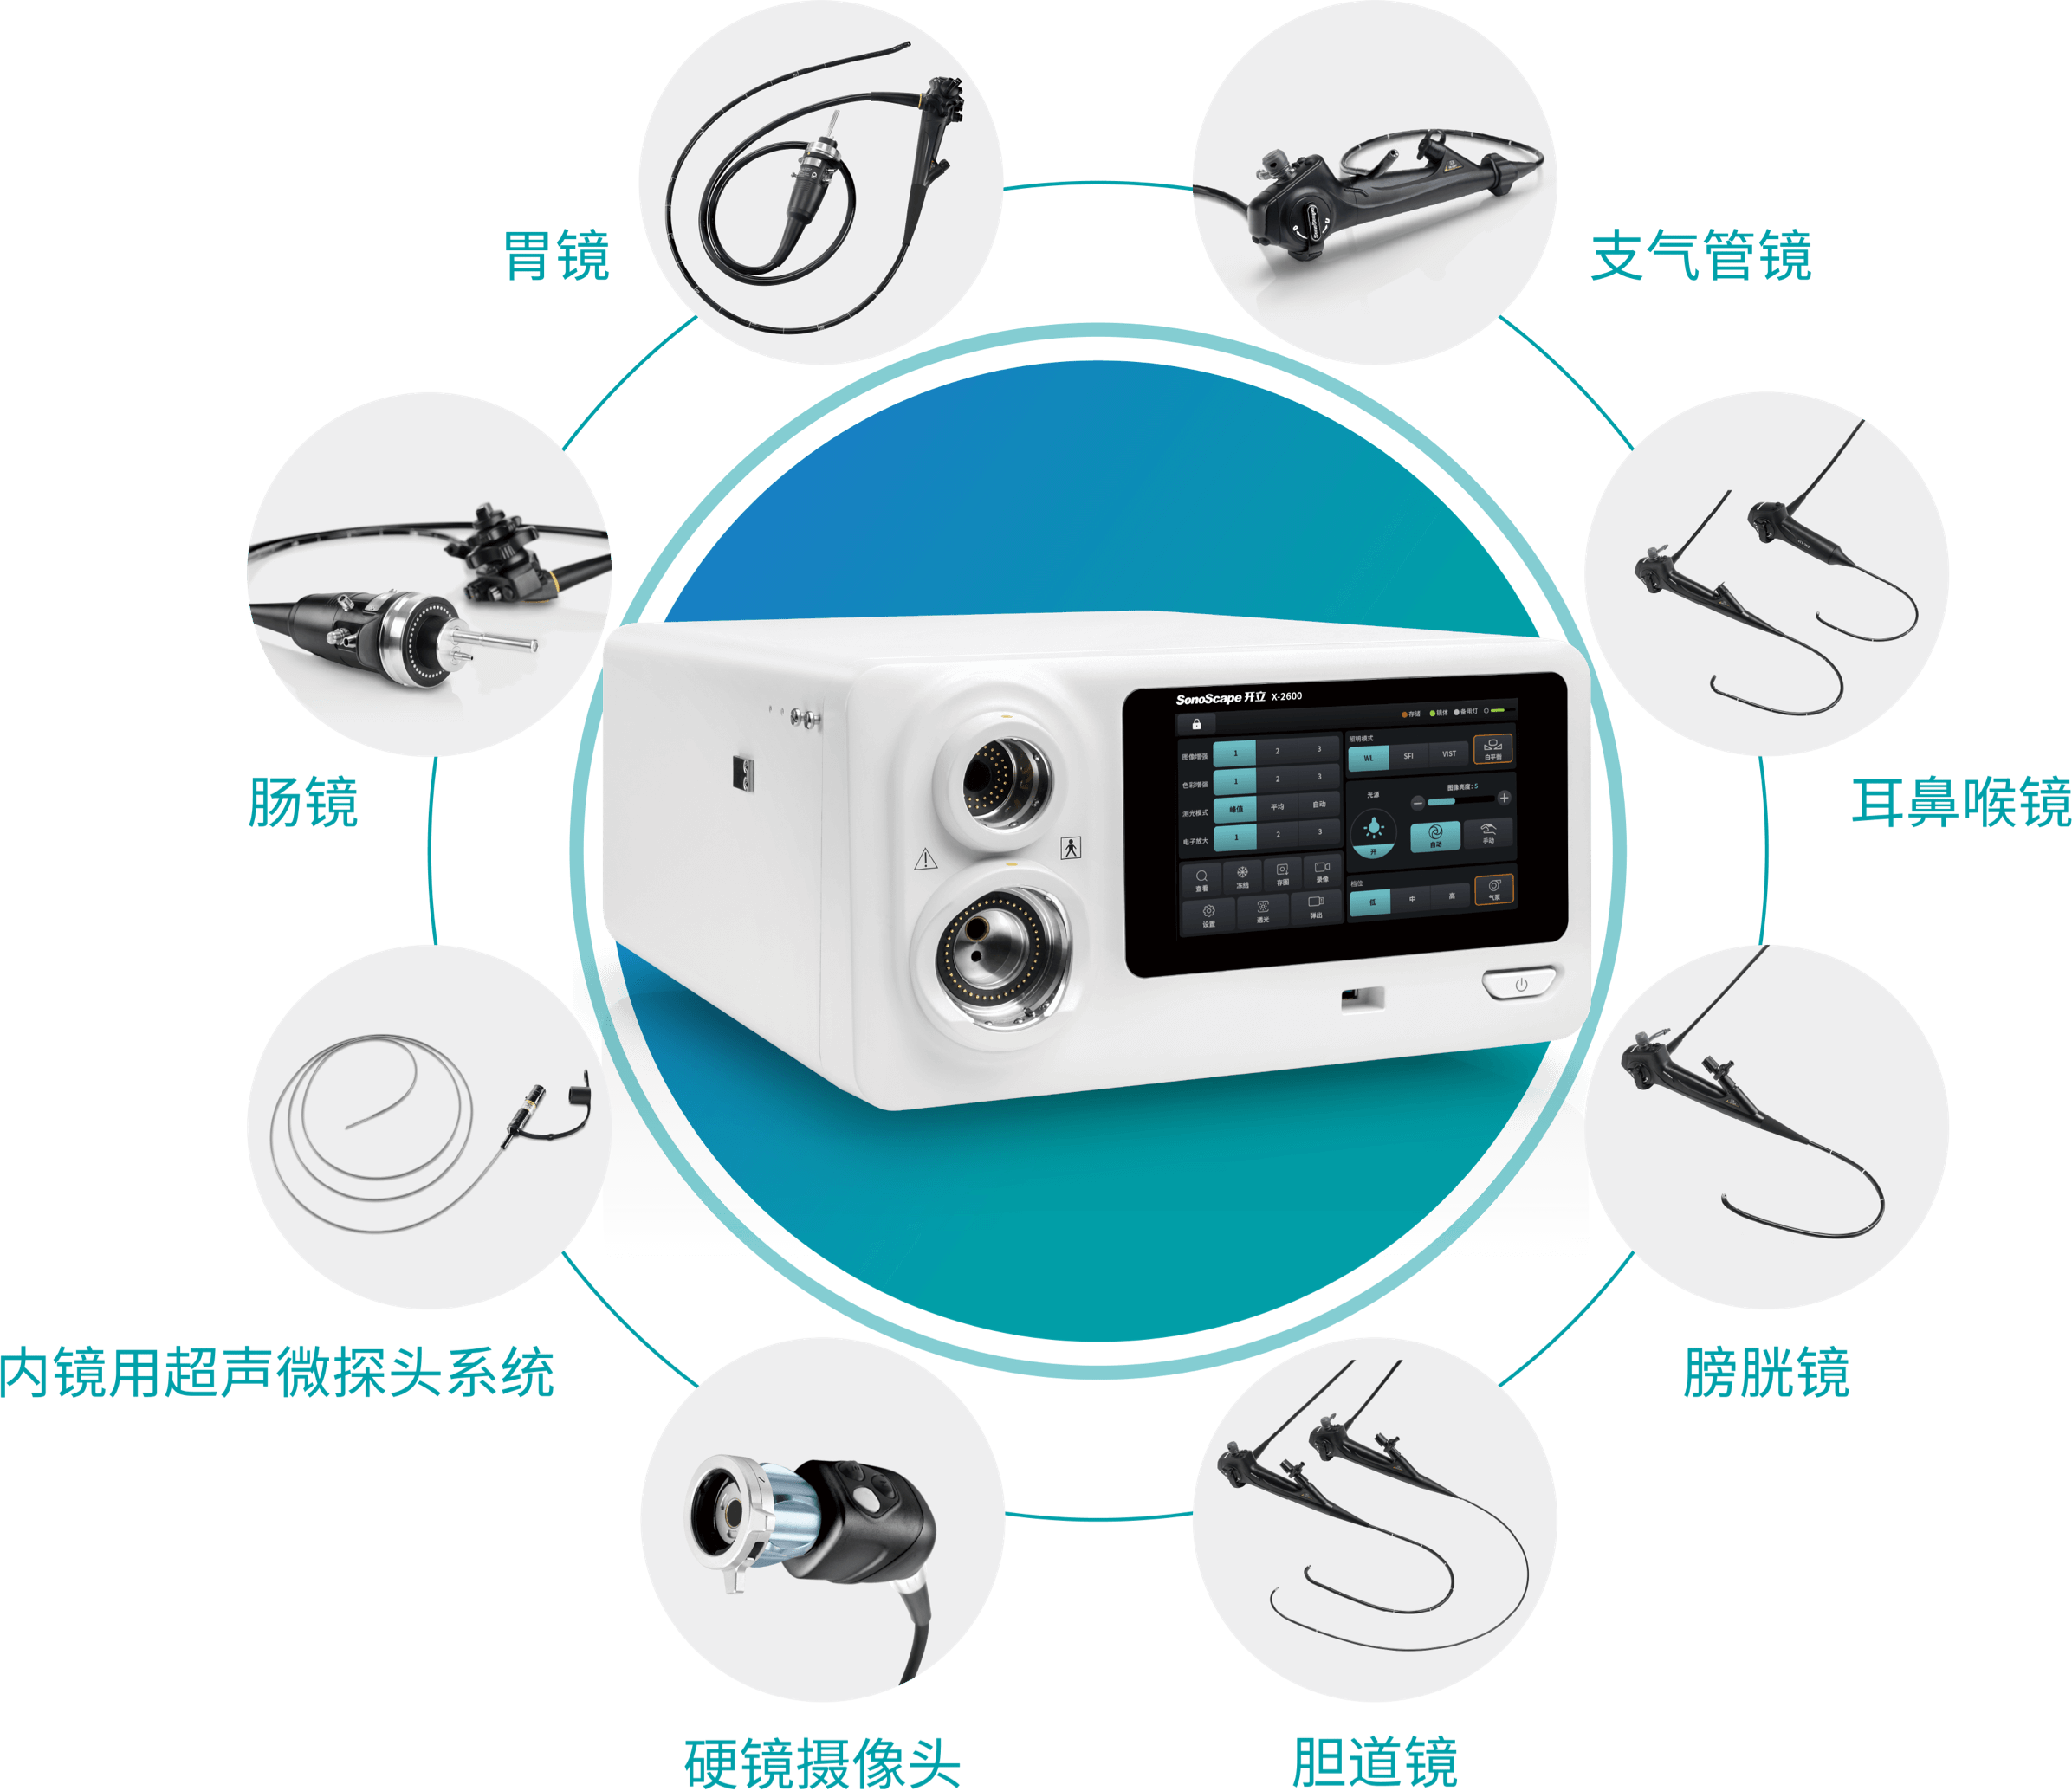

X-2600系列产品为消化呼吸内镜以及硬镜、外科软镜均支持使用的兼容性平台。医生能够根据手术需要快速切换内镜产品,更好地满足临床需求。